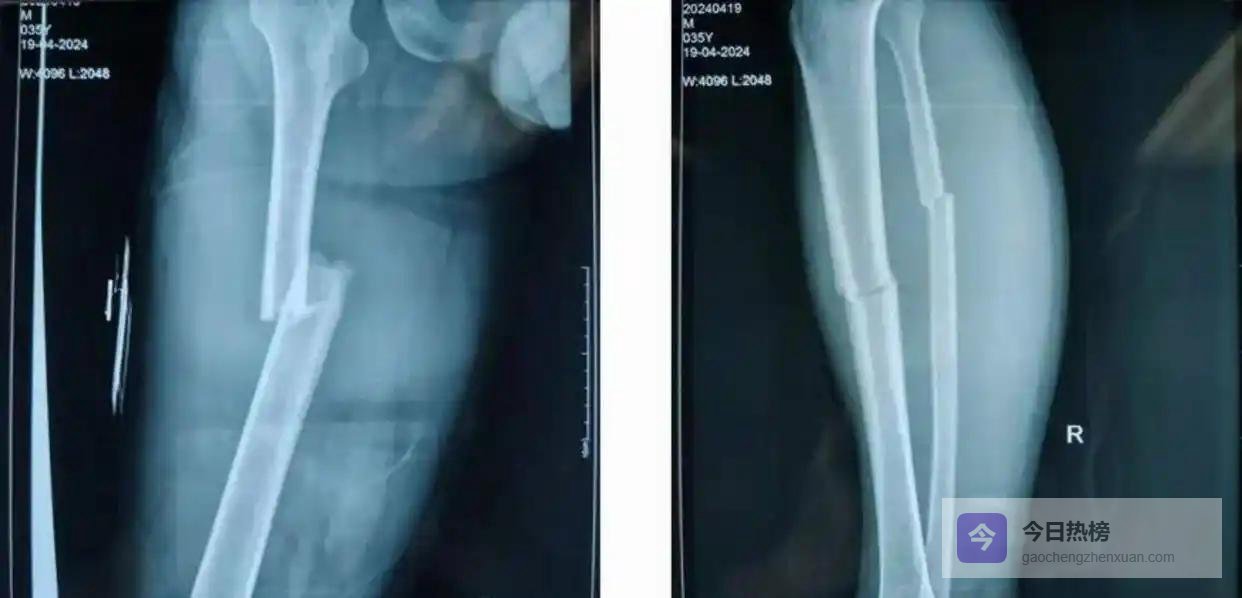

男人开车时遭遇闯红灯的大货车,当场昏迷。全身多处骨折,在重症监护室抢救两天才捡回一条命。醒来后,妻子告诉他一个残酷的事实:给所有亲戚都群发通知了,没人搭理。